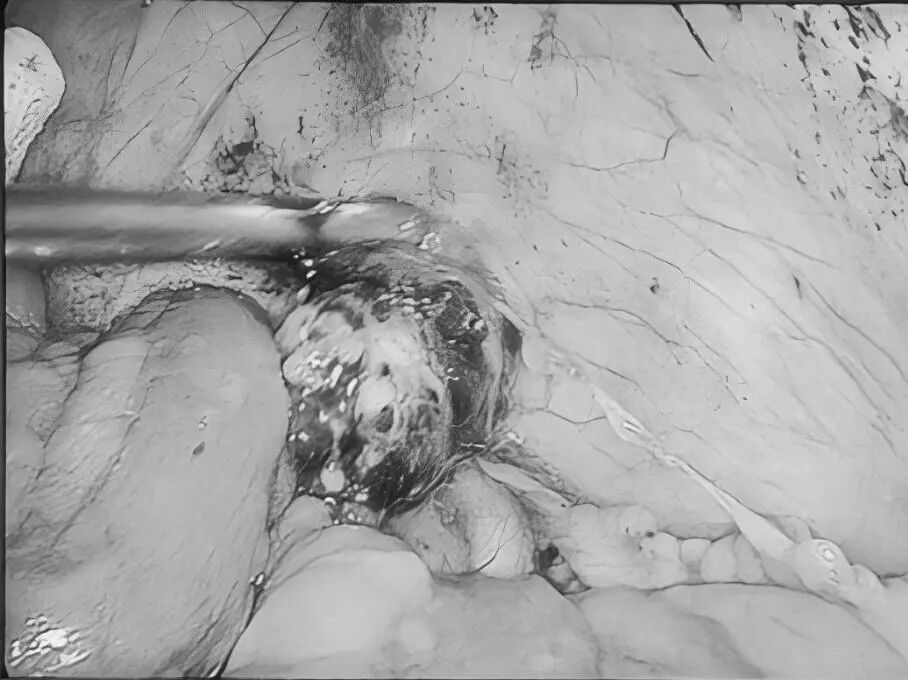

您是否正在经历 肛周肿痛、瘙痒的困扰? 是否发现过便血 或是有小肉球脱出来? 是不是因为觉得尴尬 所以一直拖着没去看? …… 这些难言之隐的背后 往往是痔疮、肛裂等 肛周疾病的信号 这些常见问题,往往与我们的日常生活习惯息息相关:长时间坐着不动、如厕时久蹲、饮食中缺乏蔬菜水果都可能增加患病风险。预防的关键在于主动调整: ✔饮食要“润”:多吃蔬菜、水果、粗粮,保证饮水,让大便保持通畅松软。 ✔久坐要“动”:每隔一小时起身活动几分钟,减轻肛周压力。 ✔如厕要“快”:减少如厕时间,避免久蹲和过度用力。 ✔清洁要“轻”:便后保持清洁,用温水冲洗或柔软纸巾轻拭。 养成良好的生活习惯,是守护肛周健康的第一道防线。 目前,治疗这类疾病的方法有很多。在贵州航天医院普外科,我们在常规诊疗基础上,进一步融入了中医调理的优势,为您提供一种更注重恢复过程中的舒适度、也更关注身体的整体调理特色方案——中西医结合治疗肛周疾病,希望能帮助您更安心、更顺畅地解决难言之隐。 【中西医结合,优势互补】 ※西医精准明确,技术微创:借助电子肛肠镜等设备清晰诊断,并运用PPH(吻合器痔上黏膜环切术)、TST(选择性痔上黏膜吻合术)等微创手术技术,精准处理病灶,创伤小、出血少。 ※中医整体调理,促进康复:通过内服外用中药,协助术后消肿止痛、促进创面愈合,并帮助调整内在体质,减少复发。 【中西医结合诊疗的优势】 ▶术前可中医干预:对处于急性炎症期的患者,先行中药坐浴、外敷等缓解肿痛,创造更好手术条件,部分患者可能因此免于手术。 ▶术中微创精准:由经验丰富的肛肠外科医生操作,注重保护正常功能组织。 ▶术后康复加速: •中药内服调理:根据个人体质开具药方,促进恢复。 •中药坐浴外治:使用科室配置的洗剂,帮助保持清洁、缓解疼痛、舒适伤口。 •专业西医护理:配合规范的伤口换药与护理,保障愈合过程顺利。 •多模式镇痛:采用中西药结合的多种镇痛方式(如口服、外用、中药制剂等),有效缓解术后疼痛,帮助您更舒适、安心地度过恢复期。 适合以下常见肛周疾病患者: 各期痔疮(内痔、外痔、混合痔)、肛裂、肛周脓肿、肛瘘、直肠息肉、肛周湿疹、肛门尖锐湿疣、肛乳头瘤、肛门狭窄、肛门失禁等。 温馨提示: 1.肛周疾病重在早发现、早干预,请不要因羞涩而延误最佳治疗时机。 2.本文仅为疾病科普与诊疗介绍,不能替代任何专业的医疗建议,如有任何健康问题,请务必及时咨询并遵从专业医生的诊疗意见。 注:部分图片来源于网络,如有侵权,请联系删除。 贵州航天医院普外科专家简介 高大勇 普外科(肛肠外科)学科带头人、名誉主任,主任医师、教授 临床擅长:对中西医结合诊治肛肠学科各种常见病、多发病及疑难杂症等具有丰富的临床经验。 原遵义市第一人民医院(遵义医科大学第三附属医院)、遵义市中医院肛肠科主任。中华中医药学会肛肠分会常委,全国中医肛肠学科名专家,中国健康促进与教育协会肛肠分会常委,中国康复医学会肛肠疾病康复专业委员会常委,中国民间中医医药研究开发协会肛肠分会副秘书长,中国医师协会中西医结合肛肠医师专业委员会常委,国家二级心理咨询师,贵州省第一批中医名医工作指导老师,遵义市名中医,遵义市肛肠学会会长,遵义市肛肠质控中心名誉主任,遵义市中西医结合学会名誉会长,遵义市健康科普专家,原贵州省中西医结合学会肛肠分会副主任委员、贵州省中医肛肠质控中心副主任、遵义市医学会医疗鉴定委员会专家、遵义市卫生系列高评委。发表论文30余篇,主编和参编医学著作5本,主持省级科研课题2项、市级科研课题2项、院级科研课题1项。 梁 跃 普外科党支部书记、主任,主任医师 临床擅长:对普外科各类肿瘤手术具有丰富的临床经验。 毕业于遵义医学院,遵义市医学会小儿外科学分会常务委员,遵义市肛肠协会理事,遵义市医学会核医学分会(第二届)委员会委员;荣获第三期“黔医人才计划”优秀学员称号;主持市级课题1项,完成省级课题1项,在国内各类刊物上发表论文10余篇。 钱科洪 民盟盟员,普外科副主任医师 临床擅长:从事普外科临床工作30余年,对各类普外科疾病的诊治、乳腺、甲状腺、胃十二指肠、结直肠等疾病及疑难杂症具有丰富的临床经验。 毕业于遵义医学院临床医疗系,2009年前往中山大学附属第一医院微创外科进修学习,在国内各专业期刊发表论文数篇。 贵州航天医院普外科简介 基本情况 贵州航天医院普外科成立于1968年,前身属于航天部O61基地3417医院外一科,1998年3417医院、3427医院合并后更名为普外科,下设胃肠外科、肛肠外科2个亚专业科室,拥有在全市较为先进的专科设备和技术,是中国疝病专科联盟单位,贵州医科大学附属医院胃肠外科专科联盟单位。开放床位40张,配备医护人员21人。 专科特色 普外科致力于胃肠及肛肠疾病的外科临床诊治及科研,以腹腔镜微创外科技术为本,形成以快速康复治疗胃肿瘤、结直肠肿瘤、小肠肿瘤、直肠脱垂、肥胖病、急腹症、各类疝、痔、瘘等专科特色,同时注重胃肠疾病尤其是结直肠恶性肿瘤的基础研究和临床转化研究,总体诊断和治疗水平在区域同级医院居于领先水平。 开展手术:腹腔镜下胃癌根治术,腹腔镜下袖状胃切除术,腹腔镜下胃肠道间质瘤切除术,腹腔镜下结、直肠癌根治术,胃癌、结直肠癌的精准治疗,腹腔镜下小儿疝气、成人疝修补术,腹腔镜下阑尾手术,内痔的硬化注射治疗及痔疮的微创治疗:ATH、PPH、TST,直肠脱垂的各种手术治疗,难治性伤口VSD技术,鼻胃肠管、肠梗阻导管置入术,肛肠术后间歇性导尿技术,并引进了中医适宜技术,也为各种化疗患者提供输液港安装,提高患者就医体验。 腹腔镜下腹股沟疝 无张力修补术 腹股沟疝里金斯坦 (Lichtenstein)手术 PPH微创术治疗环状混合痔 黏连性或炎性肠梗阻-肠梗阻导管 腹腔镜袖状胃切除 腹腔镜阑尾切除术 腹腔镜阑尾肿瘤切除术 腹腔镜下结肠癌根治术 诊疗范围 胃肿瘤、结直肠肿瘤、小肠肿瘤、肥胖症、各类急腹症、腹部外伤、腹壁疝、便秘、直肠脱垂、痔疮、肛瘘、肛裂等胃肠、肛肠外科疾病。 END